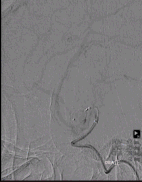

多角度造影提示动脉瘤颈造影剂滞留,瘤体不显影,右侧大脑中动脉各分支显影良好,未见明显狭窄、闭塞。

术后造影